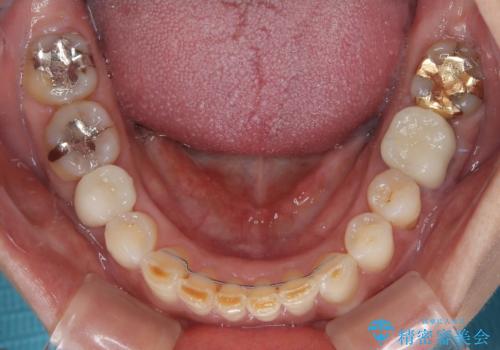

咬合力が非常に強く、全体的に歯が擦り減っている状態であったので、理想的な咬み合わせを達成することは難しく、また咬合力が強い方のマウスピース矯正は、思い通りに動かないことがあるため、ワイヤー矯正の方が望ましいように思えました。

治療途中で2年強、体調を崩されて通院ができなくなってしまったため、必ず通院が必要なワイヤー矯正ではなく、マウスピース矯正で結果的には無事に治療を終えることができました。